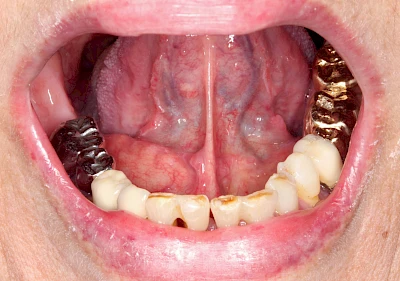

Milchiges bzw. gelbliches Sekret im Bereich der Speichelausführungsgänge entweder an den Wangeninnenseiten auf Höhe der ersten großen Backenzähne im Oberkiefer oder unter der Zunge können auf Entzündungen der großen Spreicheldrüsen hinweisen. Ebenso Schwellungen bzw. Auftreibungen, Rötungen oder spürbare Wärme einseitig unterhalb eines Ohrs und im Bereich des Kieferwinkels.

Speicheldrüsenzyste

Eine Speicheldrüsenzyste (Speicheldrüsenretentionszsyte) kann als Schwellung oder Auftreibung meist im Bereich der größeren Ausführungsgängen auffallen, wenn z. B. ein Speichelstein den Speichelfluss behindert. Vor allem bei den Mahlzeiten, wenn der Speichelfluss angeregt wird, nimmt die Auftreibung oder Schwellung schmerzhaft weiter zu. In der Regel ist die Unterkieferspeicheldrüse (Glandula sublinugalis) betroffen. Man spricht dann auch von einer Frosch- bzw. Fröschleingeschwulst (Ranula). Bringt sanftes Massieren der Schwellung bzw. Auftreibung keine Verbesserung, sollte ein Arzt oder Zahnarzt hinzugezogen werden